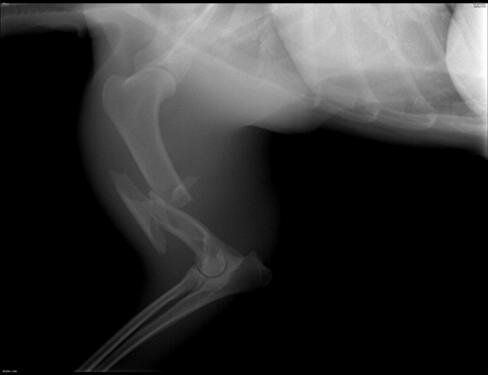

Сложный спиралевидный оскольчатый перелом диафиза плечевой кости

Плечевая кость после накостного остеосинтеза пластиной, проволочным серкляжем и кортикальными винтами

Большей диагностической ценностью является рентгенография конечности/конечностей. При рентгенографии конечностей необходимо выполнять рентген в двух взаимно перпендикулярных проекциях (прямая, боковая). Этот метод необходим для постановки окончательного диагноза. Также следует отметить, что рентгенография не должна являться единственным методом диагностики.